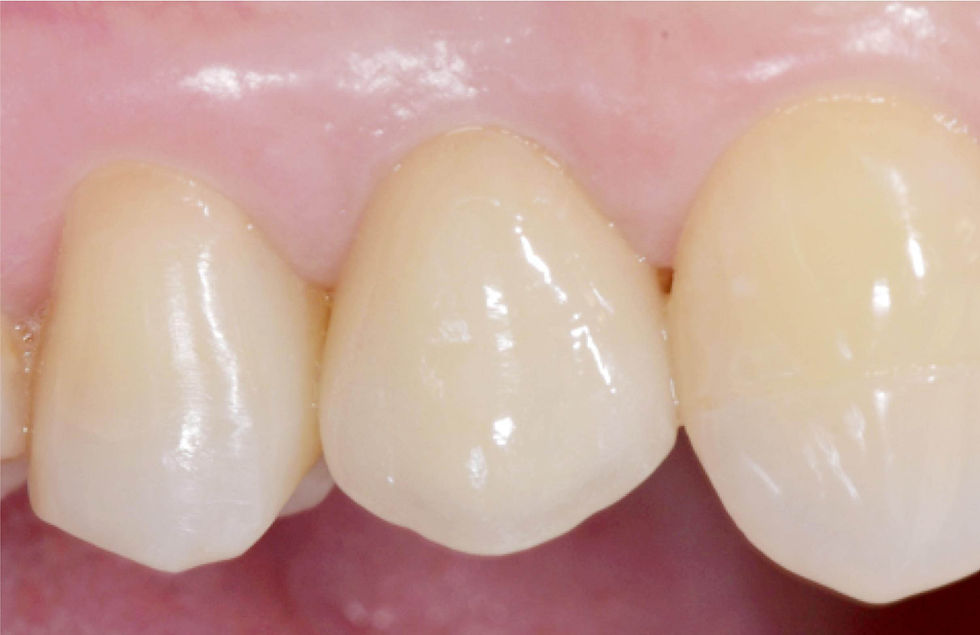

Clinical images at the delivery of the definitive crown.